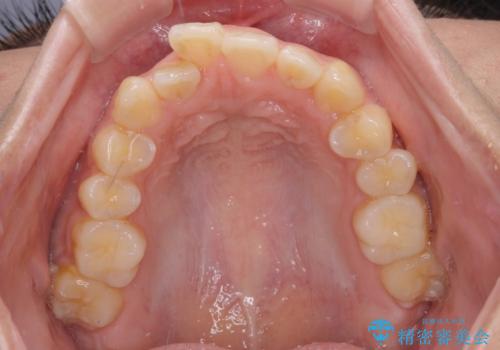

- 八重歯と、上下前歯が接触しないくらい前突した前歯を気にして来院された患者様です。

奥歯の噛み合わせは正常に近い状態でしたが、右上の奥歯に突起があったり、上下前歯が非接触であったりしていたため、補助装置を使用して上顎前歯を積極的に引っ込めるように計画しました。

口元の突出感を改善するために上下左右の小臼歯4本を抜歯し、ワイヤー装置によりデコボコを解消しながら口元の突出感も改善していくこととしました。